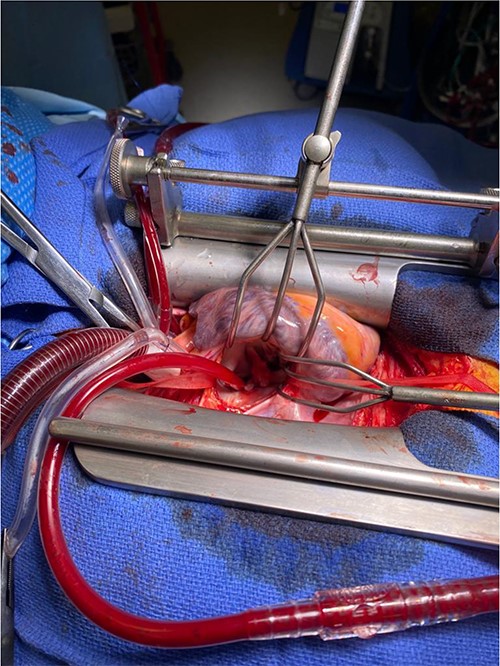

Intra-operatively, femoral–femoral bypass was established and a 3 cm windsock vegetation was found with a 1.5 × 1.5 cm hole at the aortic inlet on the annular junction. The vegetation travelled from the LV to LA as shown in Figs 3 and 4. The vegetation was excised and the valve debrided, which resulted in moderate regurgitation from severe. Hence, a further 26 mm Physio II ring was placed resulting in no mitral regurgitation. The excised vegetation is shown in Fig. 5 and the post-op TTE images are shown in Figs 6 and 7.